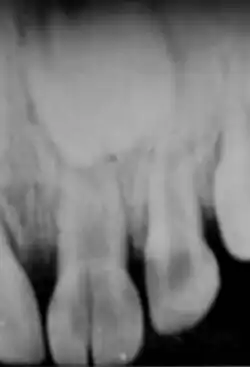

Röntgenkontrollaufnahme der fertigen Wurzelfüllung